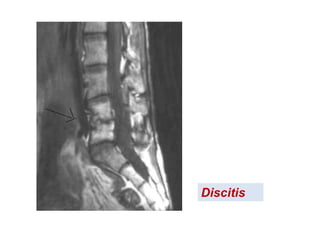

Infecciones vertebrales

CLASIFICACIÓN

OSTEOMIELITIS VERTEBRAL (ESPONDILITIS)

o Piógena

o No piógena (ej. TBC)

ABSCESO EPIDURAL

DISCITIS

Espontánea

OSTEOMIELITIS

Osteomielitis tuberculosa (enfermedad de Pott).